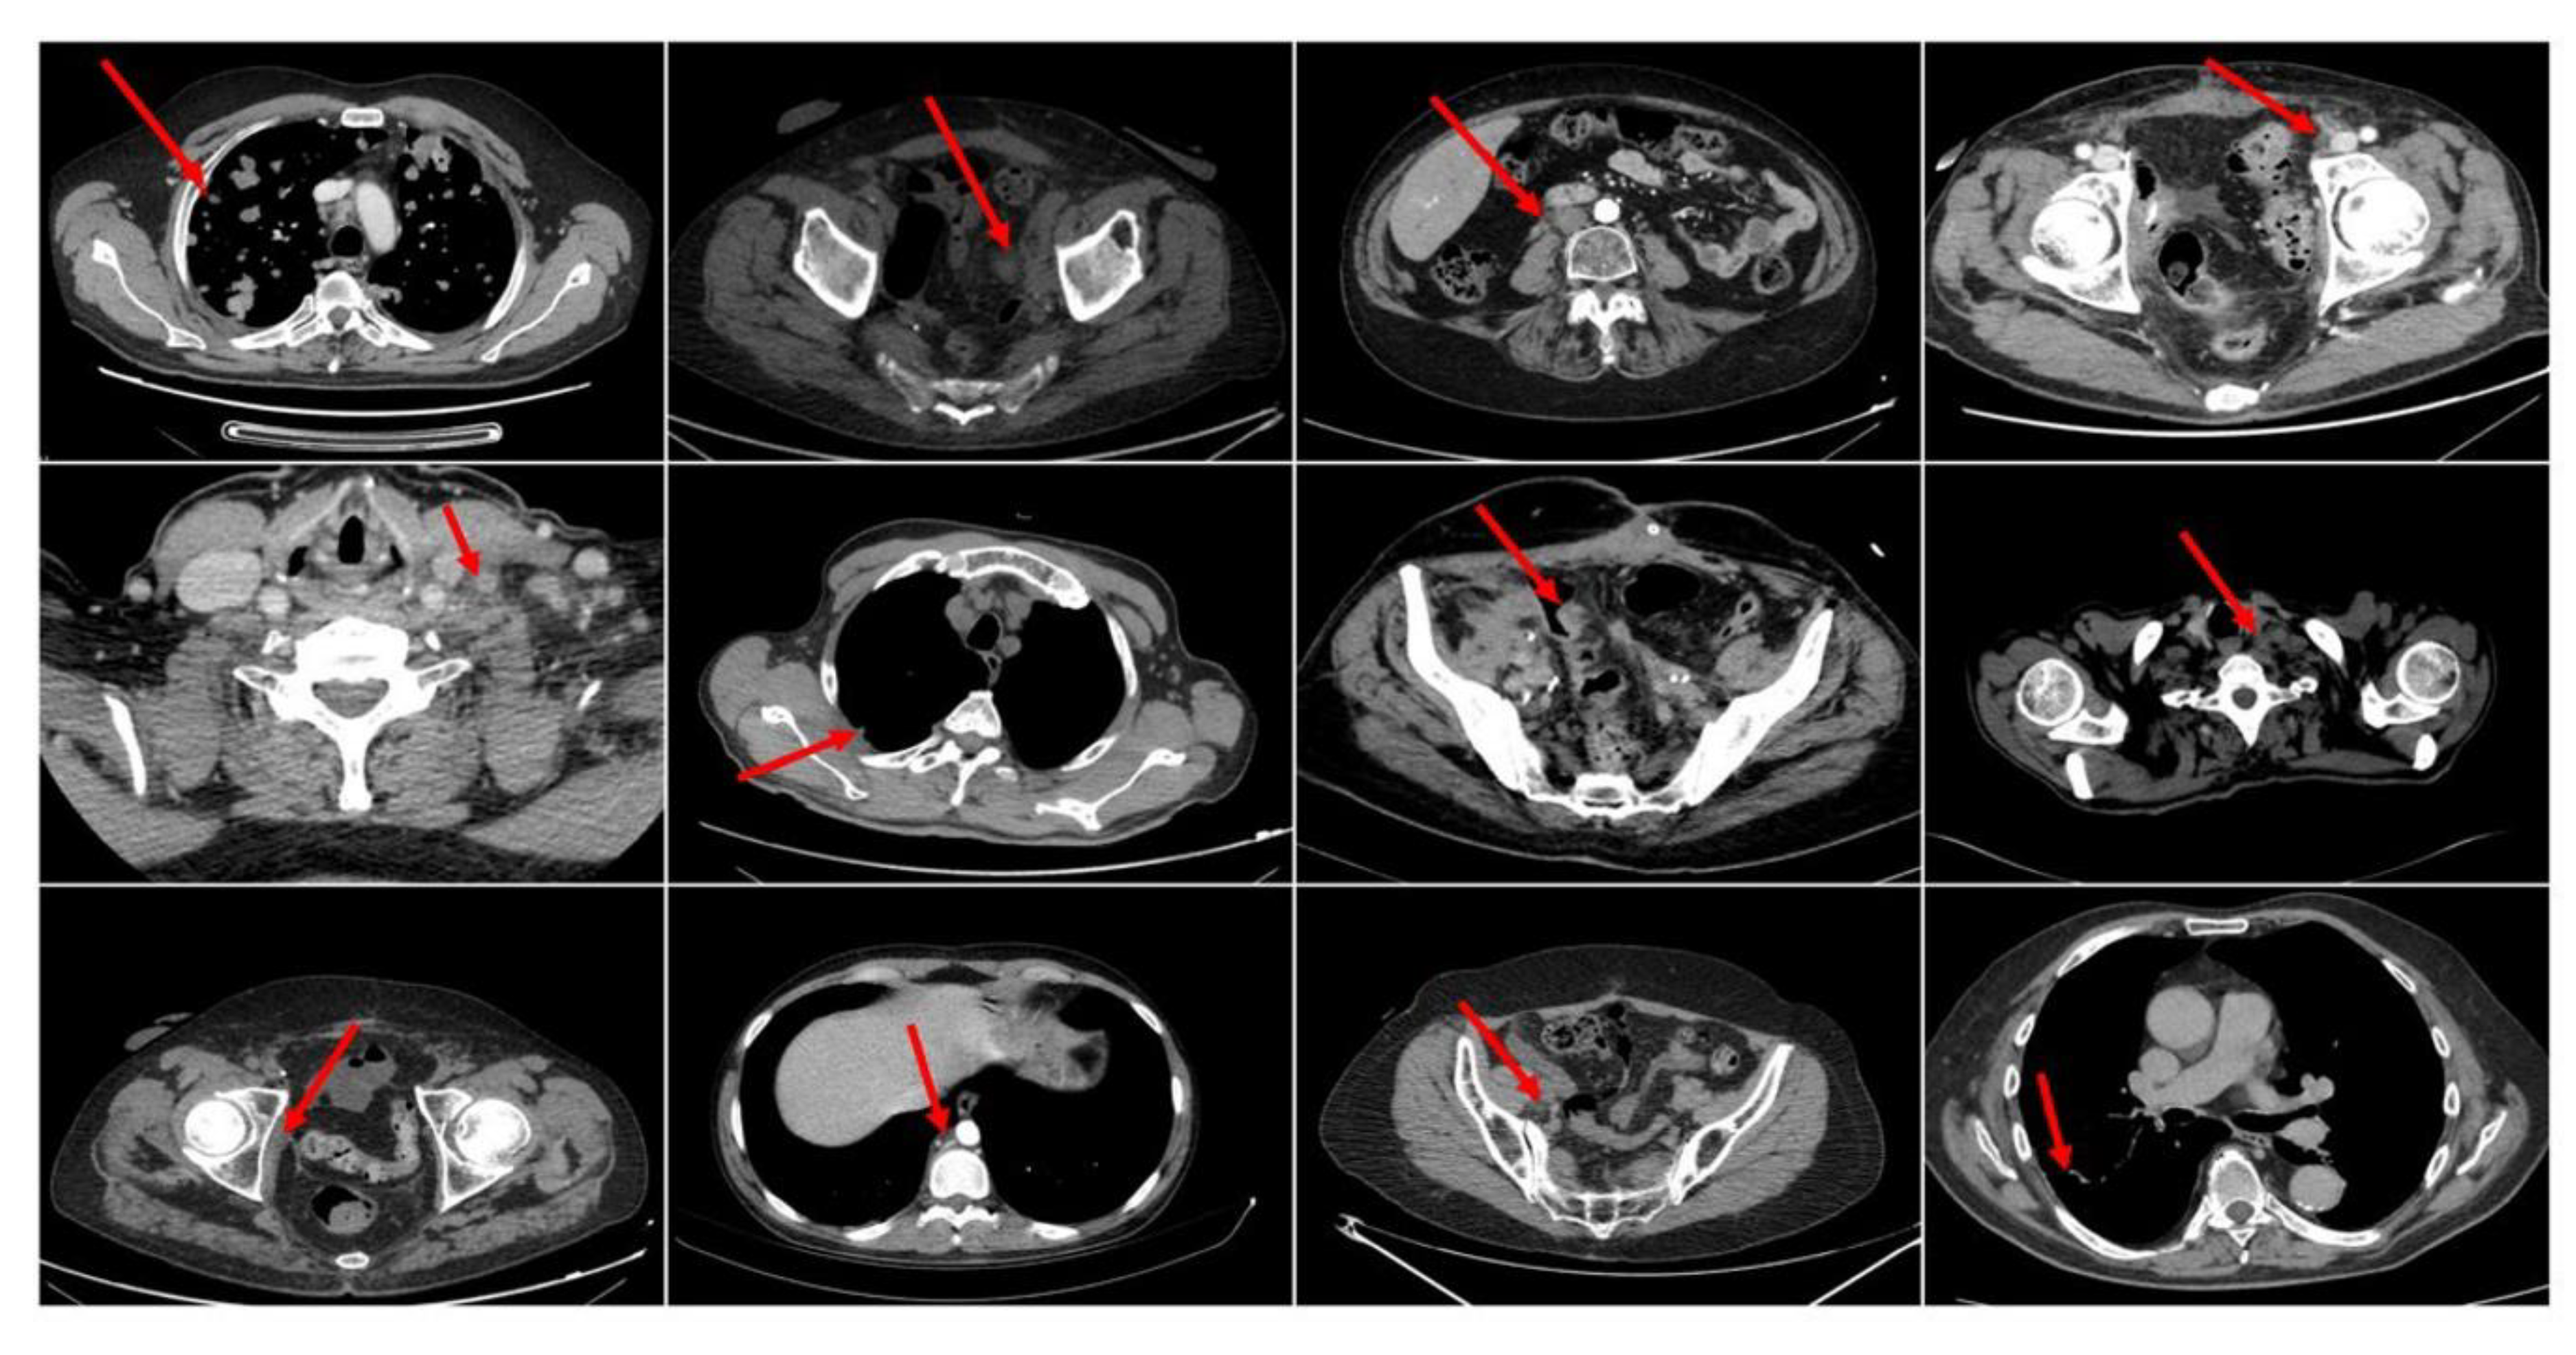

| Metastases Site | ||

| Lymph-nodes only | 14 | 33 |

| Visceral | 29 | 67 |

| Treatment Response | ||

| CR/PR/SD | 16 (43 target lesions) | 37 |

| PD | 27 (63 target lesions) | 63 |